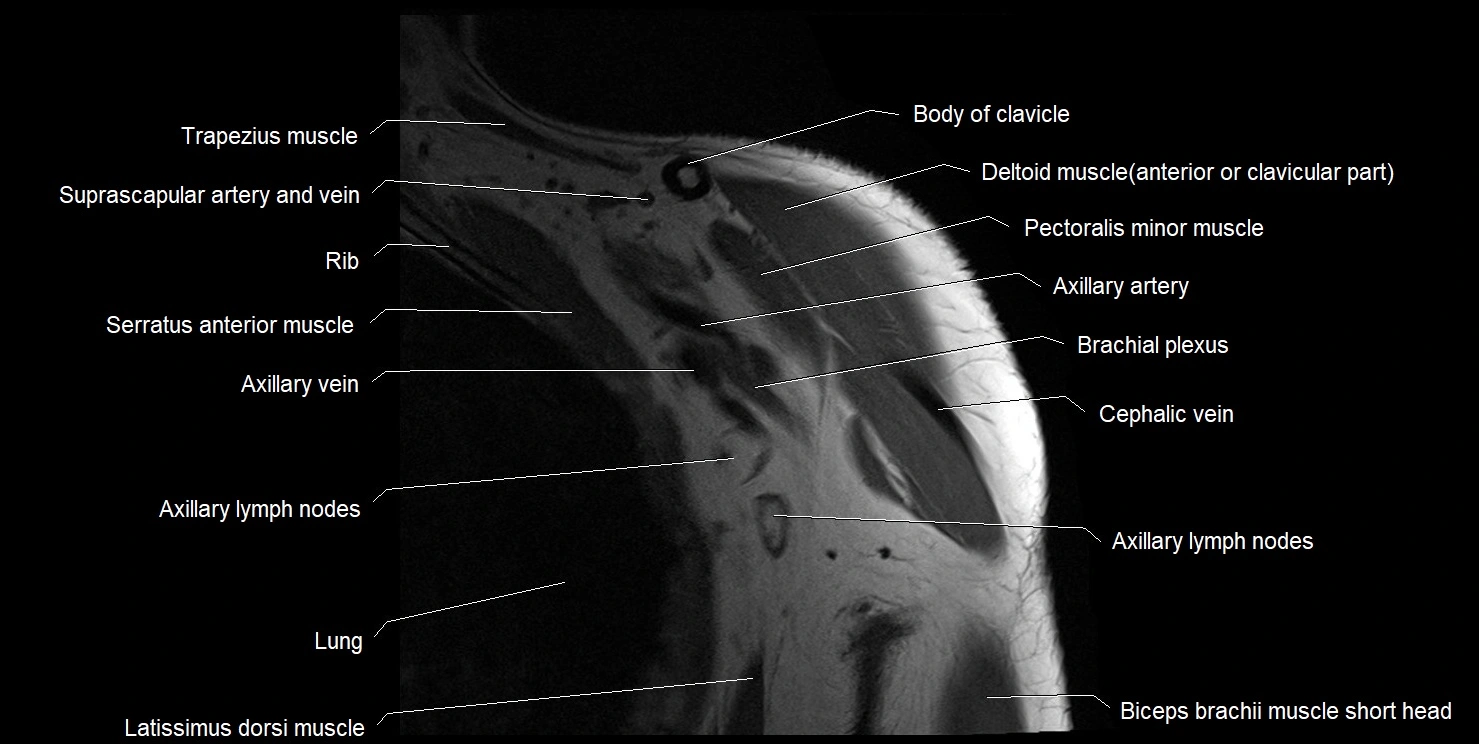

MRI images

image